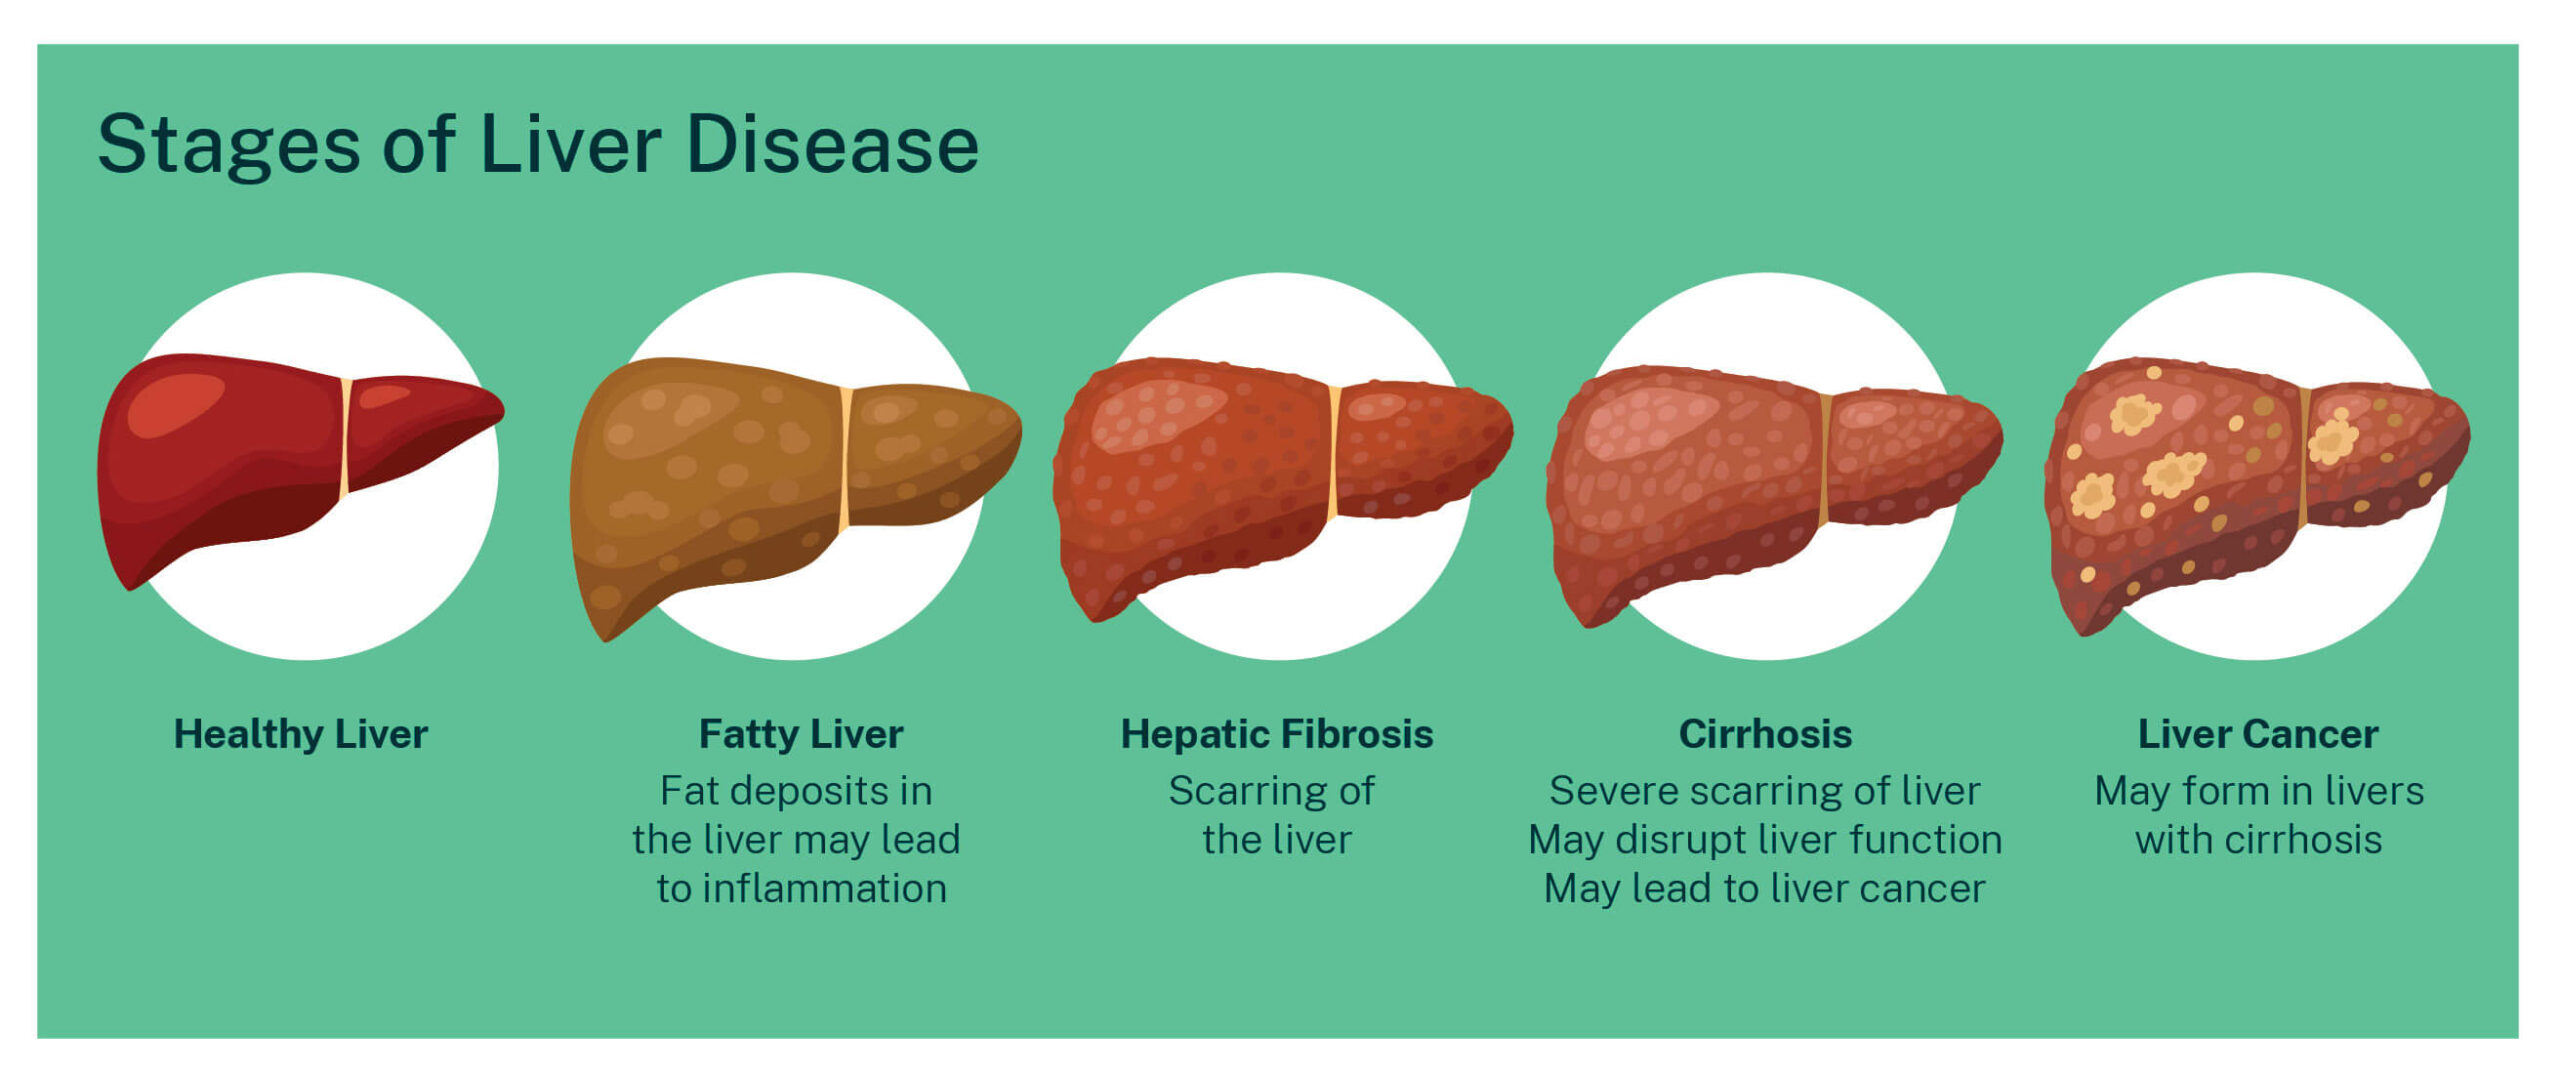

Cirrhosis Liver Foundation

https://liver.org.au/wp-content/uploads/2022/12/Stages_of_liver_disease-scaled.jpg